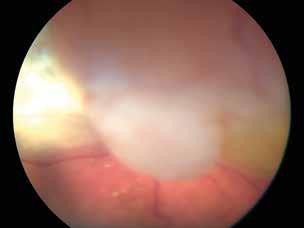

5. Multimodal imaging of a

diabetic patient affected by

5A) UWF pseudocolor retinography showing some hard exudates within and outside vascular arcades; 5B) Late phase UWF FA presenting far peripheral BRB rupture, with associated perivascular leakage and retinal ischemia, and diffuse pooling effect within telengectasic vessels; 5C) UWF SS-OCT, displaying some hard exudates close to optic disc.

OCT-A) (Figures 2-5).